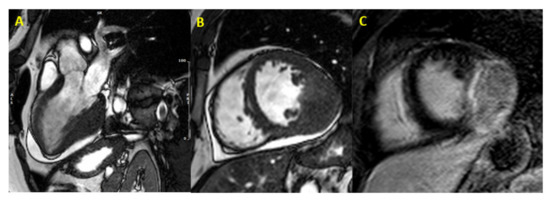

- Moscatelli, S.; Nardi, B.; Indolfi, E.; Fazzari, F.; Montini, O.; Coppini, L.; Monti, L. P586An unusual phenocopy of hypertrophic cardiomyopathy: A case report. Eur. Heart J. Cardiovasc. Imaging 2019, 20, 586. [Google Scholar] [CrossRef]